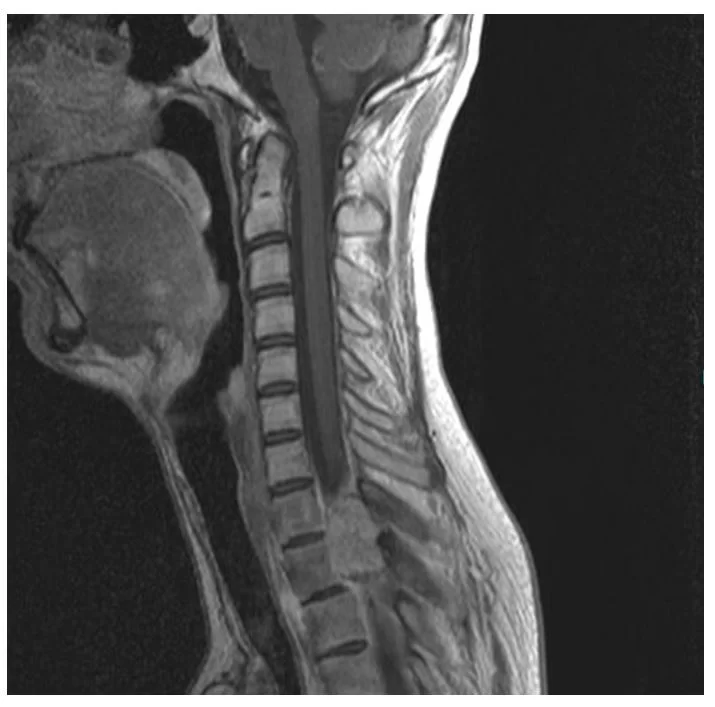

Σύνδρομο Chiari – Συριγγομυελία

Νεαρή ασθενής 17 ετών με εκτεταμένη συριγγομυελία από την αυχενοπρομηκική συμβολή έως το τελικό τμήμα του νωτιαίου μυελού, λόγω συνδρόμου Chiari. Κλινικά αιμωδίες (μουδιάσματα) άνω